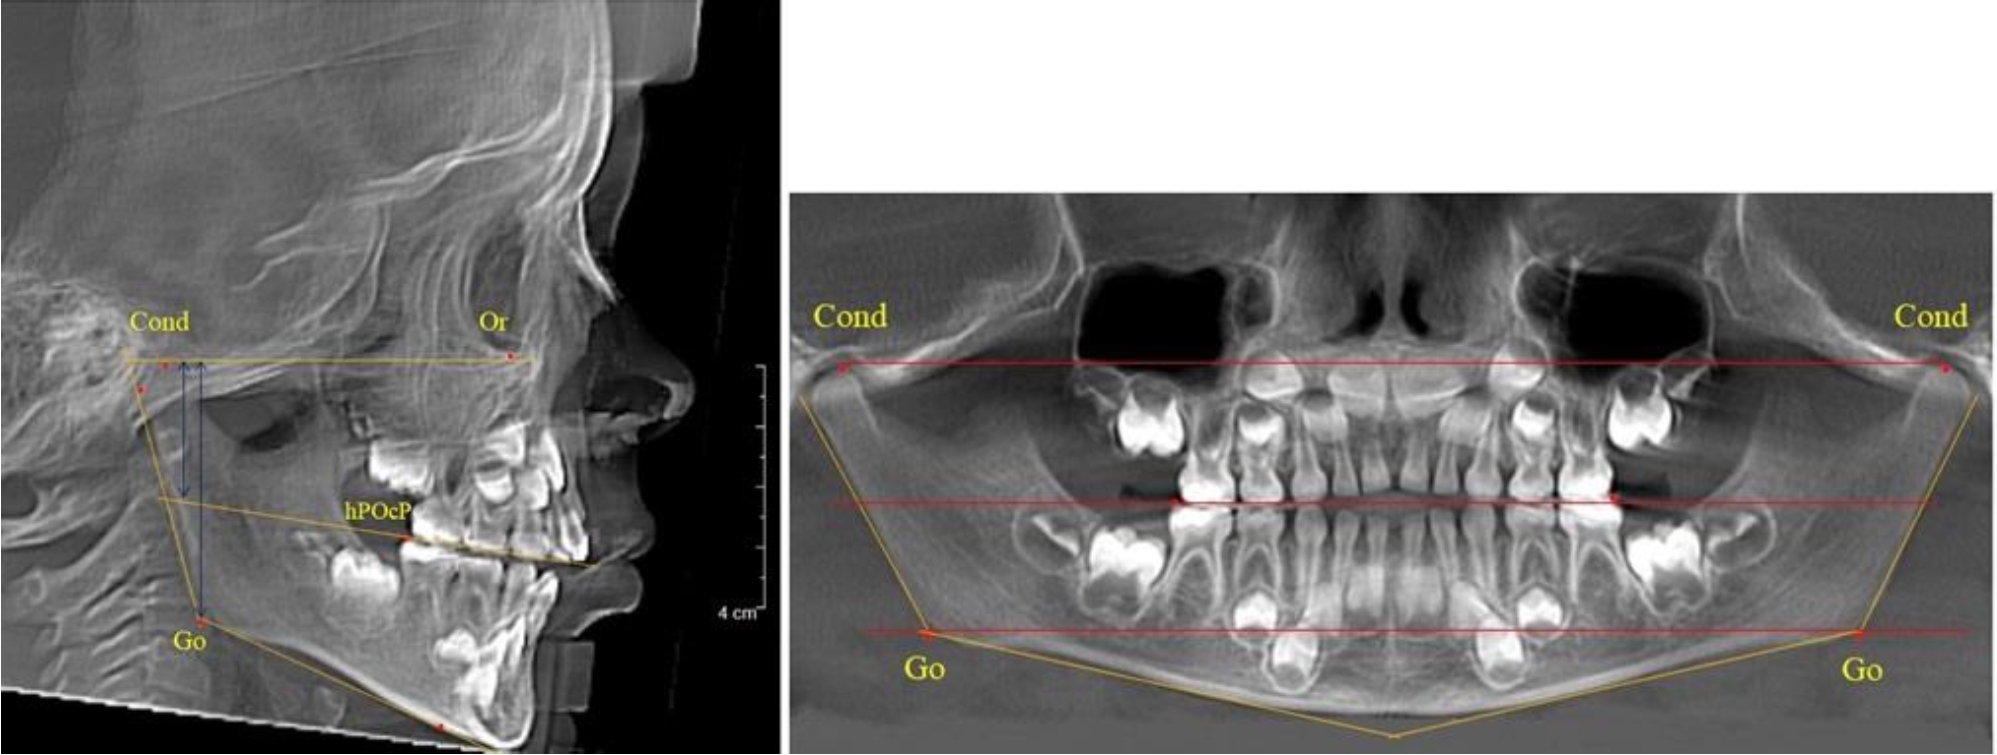

Во 2-й группе были проанализированы 11 телерентгенограмм и 11 ортопантомограмм, что составило (10,38 ± 2,96) % от числа изученных рентгенограмм. На всех рентгенограммах первые постоянные моляры были установлены в окклюзии, и произошла смена нижних медиальных резцов.

На всех парах рентгенограмм угол нижней челюсти, измеренный на телерентгенограмме, так же, как и в 1-й группе, соответствовал углу, полученному при построении угла на ортопантомограмме. Окклюзионная линия делила ветвь на два отдела (рис. 2).

Рис. 2. ТРГ и ОПТГ пациента после прорезывания первых постоянных моляров

Как на ортопантомограмме, так и на телерентгенограмме высота ветви у детей 2-й группы составляла (46,54 ± 2,87) мм, что было несколько больше, чем у детей 1-й группы (р ˂ 0,05). При этом высота верхней окклюзионно-суставной части была (25,42 ± 1,59) мм, а нижней – (21,12 ± 1,77) мм.

Таким образом, верхняя часть была несколько больше нижней, что и определяло рост обеих частей ветви.

Относительные показатели соразмерности частей ветви нижней челюсти показали, что отношение высоты верхней части ветви к нижней в среднем составляло 1,21 ± 0,12. Отношение общей высоты ветви к верхней ее части составляло 1,83 ± 0,13, а отношение общей высоты ветви к нижней ее части было 2,20 ± 0,16, и достоверных различий по относительному показателю отношения всей высоты к верхней и нижней челюсти нами не отмечено (р ˃ 0,05).